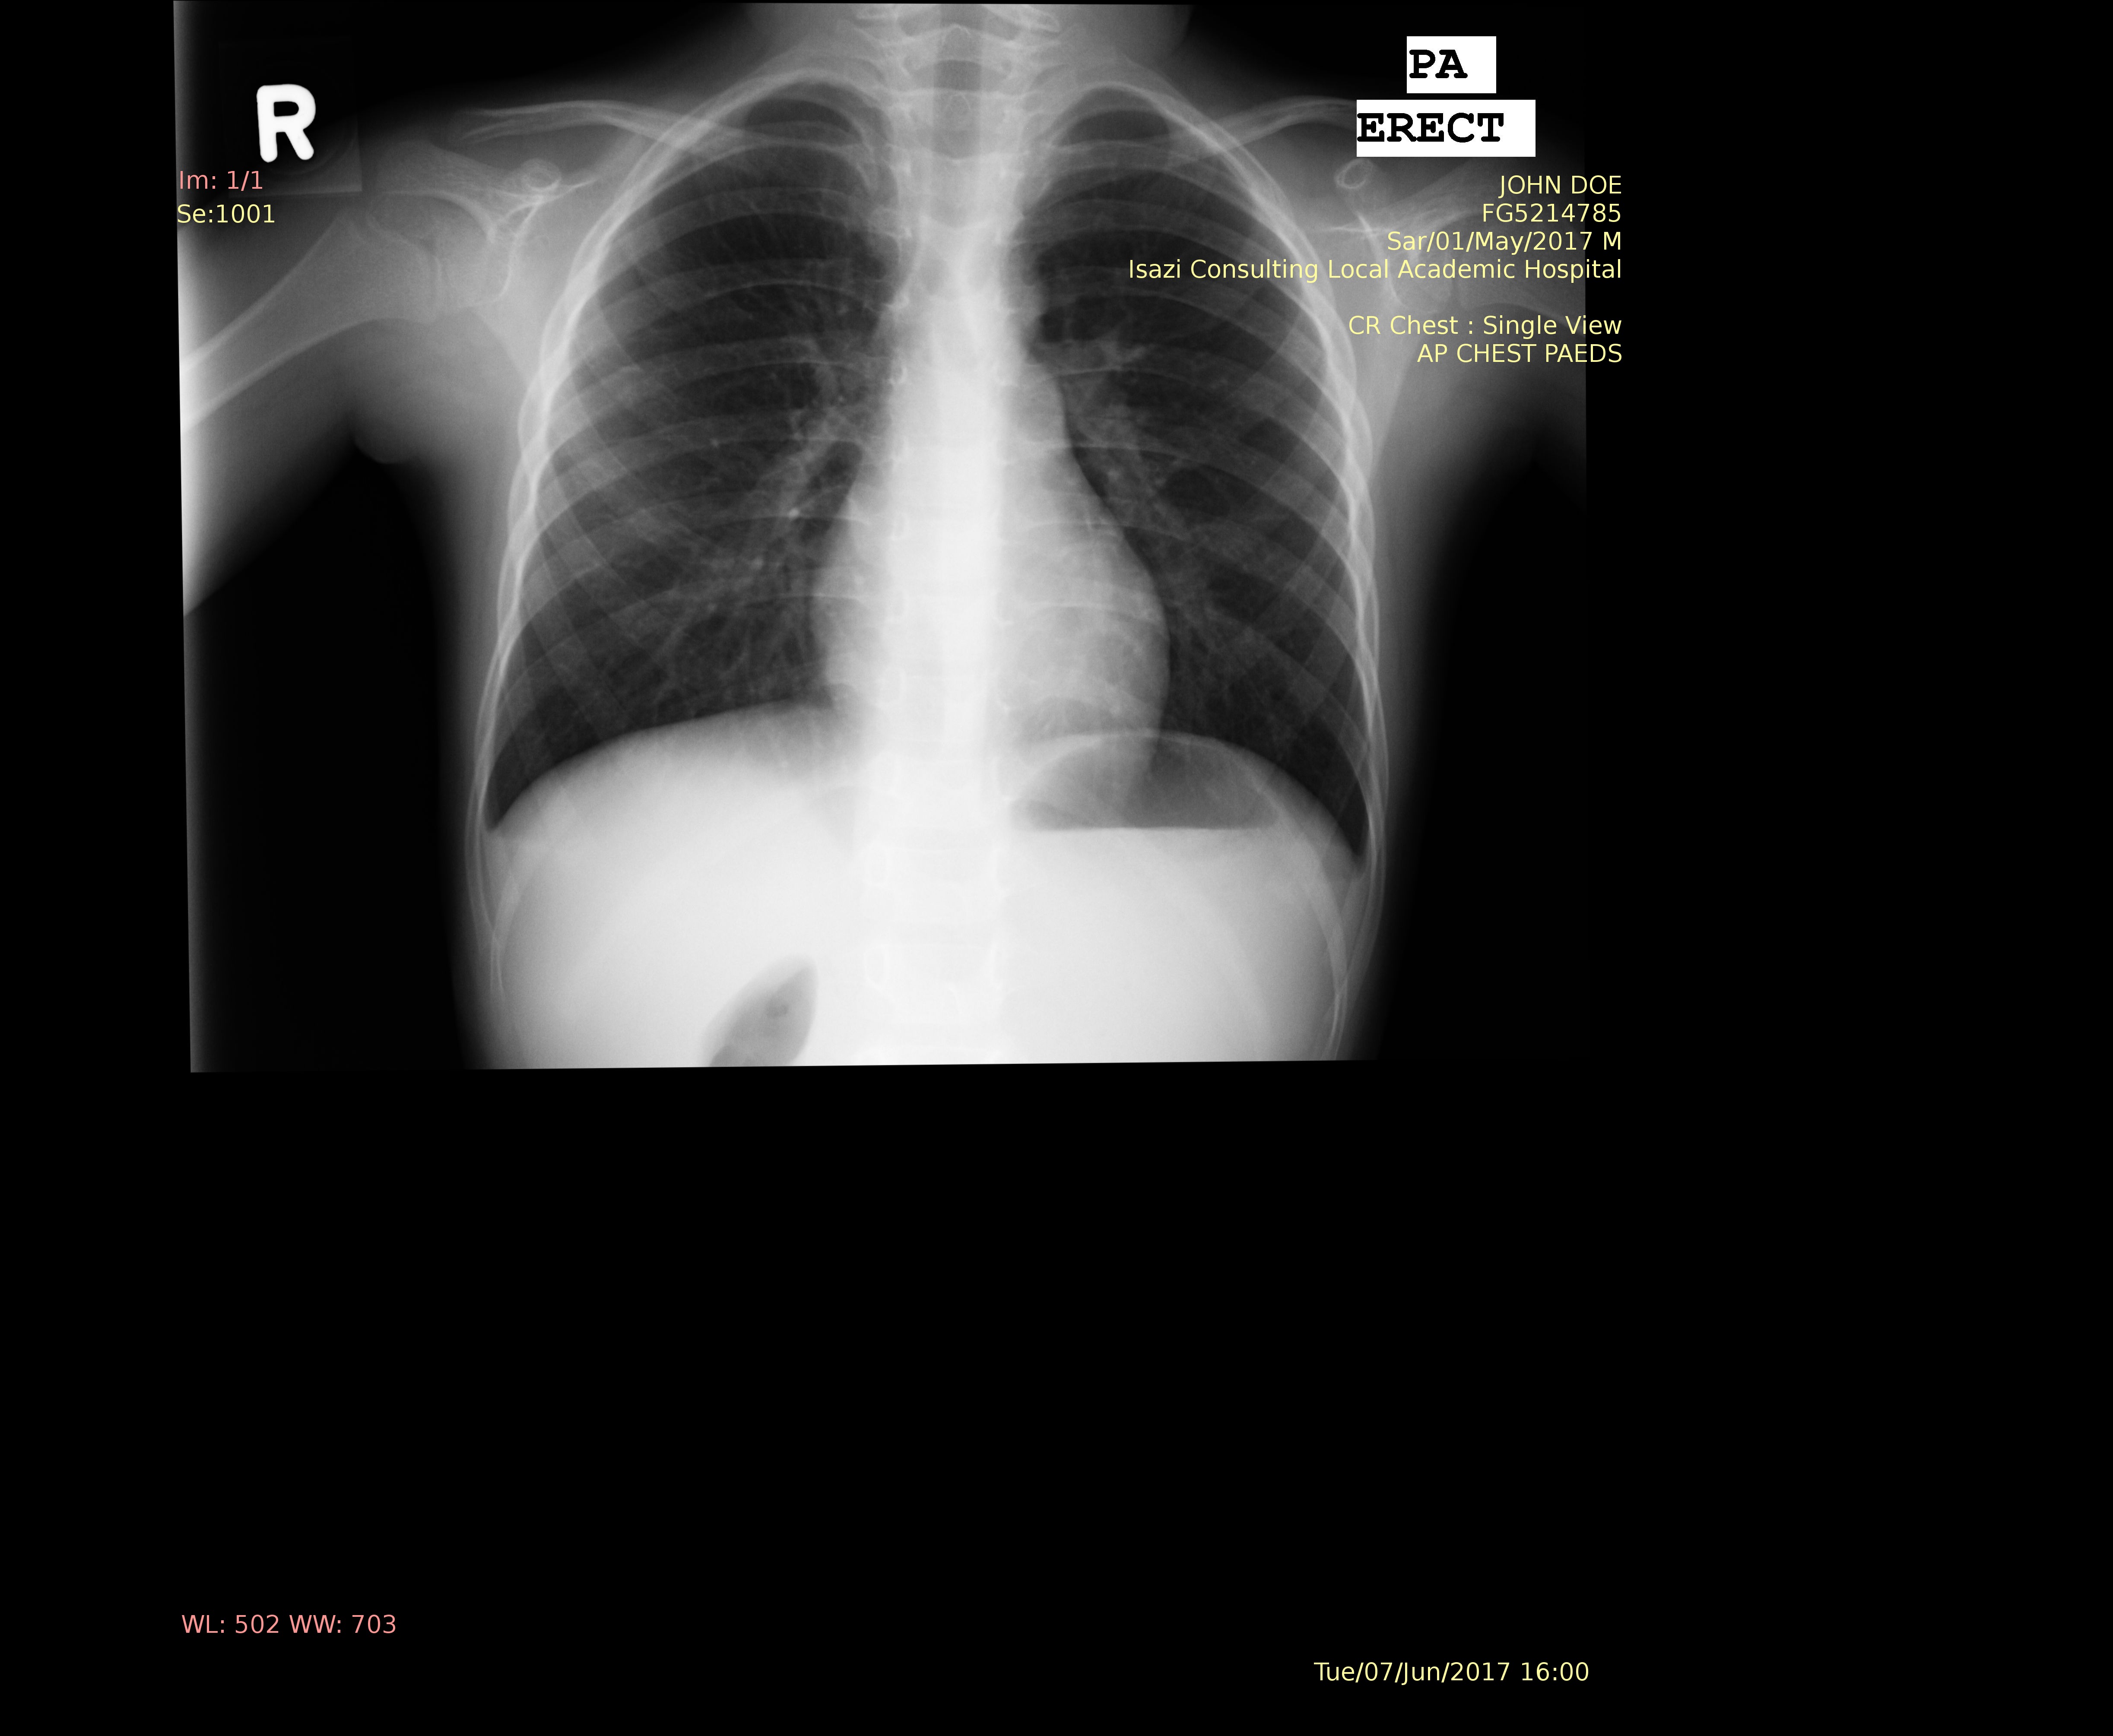

The raw data that we were receiving would be an x-ray arbitrarily placed on a black background with the sensitive patient information written across the x-ray in a yellow colour, much like the image seen below.

NOTE: The image below was obtained from the Montgomery County chest x-ray set and fake text was imposed onto the image

X-Ray containing sensitive information

Fig 1. - Raw x-ray sample